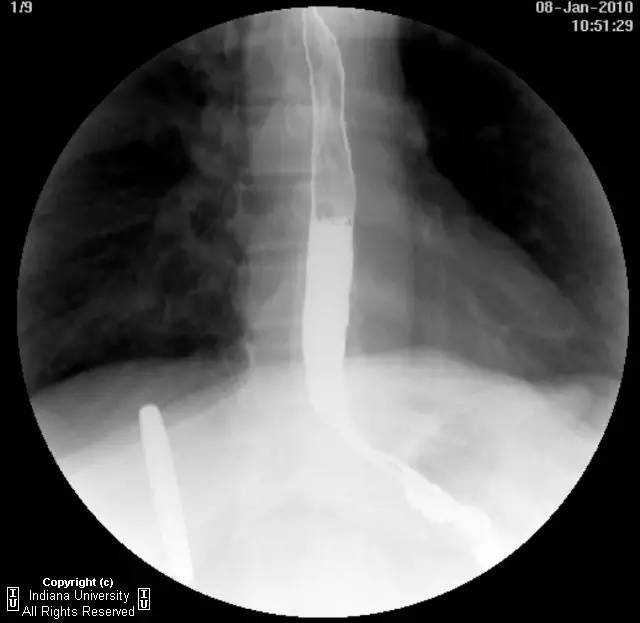

【影像学表现】下咽部正常,环咽肌功能正常。颈段食管无外生性病变压迫或异常扩张。胸中段食管长节段狭窄,逐渐移行为正常食管粘膜。大量小的烧饼样钡斑位于相应食管外呈浮萍样,与食管管腔无直接交通。稠或稀钡剂通过均无延迟。1cm钡剂片延迟通过,约30分钟后自动溶解。余食管动力正常。

【诊断】食管壁内假性憩室并长节段狭窄

Long segmentstricture with esophageal intramural pseudodiverticulosis